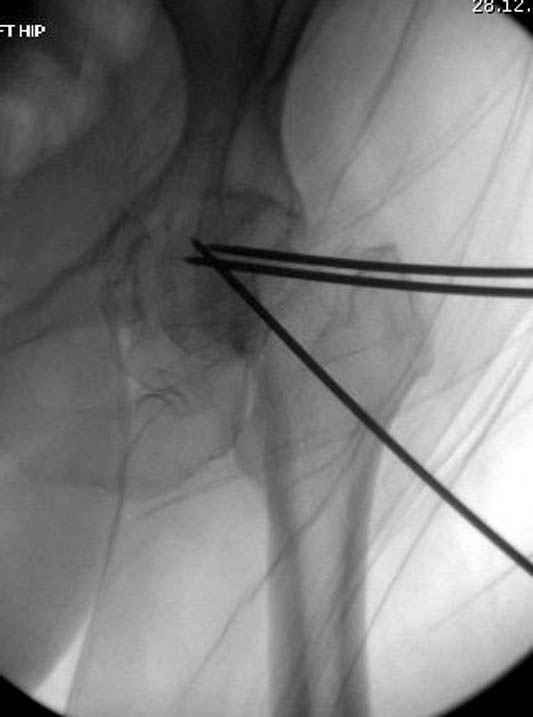

Фиксацию шейки провели когда получили окно, быстро

перкутанно смогли провести шурупы.

Перелом шейки смогли зафиксировать через пару дней, ацетабулум до сих пор не оперирован, на вытяжении.